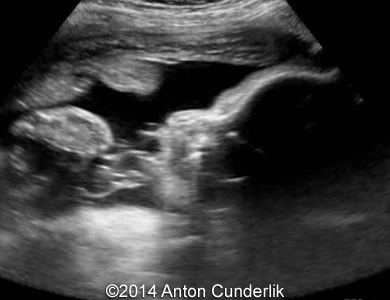

Image 1: 21 weeks of gestation. Normal fetal profile, no anomalies were found during the scan.

Image 2, 3, 4, 5, 6, 7: 30 weeks of gestation; the images show cystic structure within the fetal tongue that later turned out to be thyroglossal cyst.